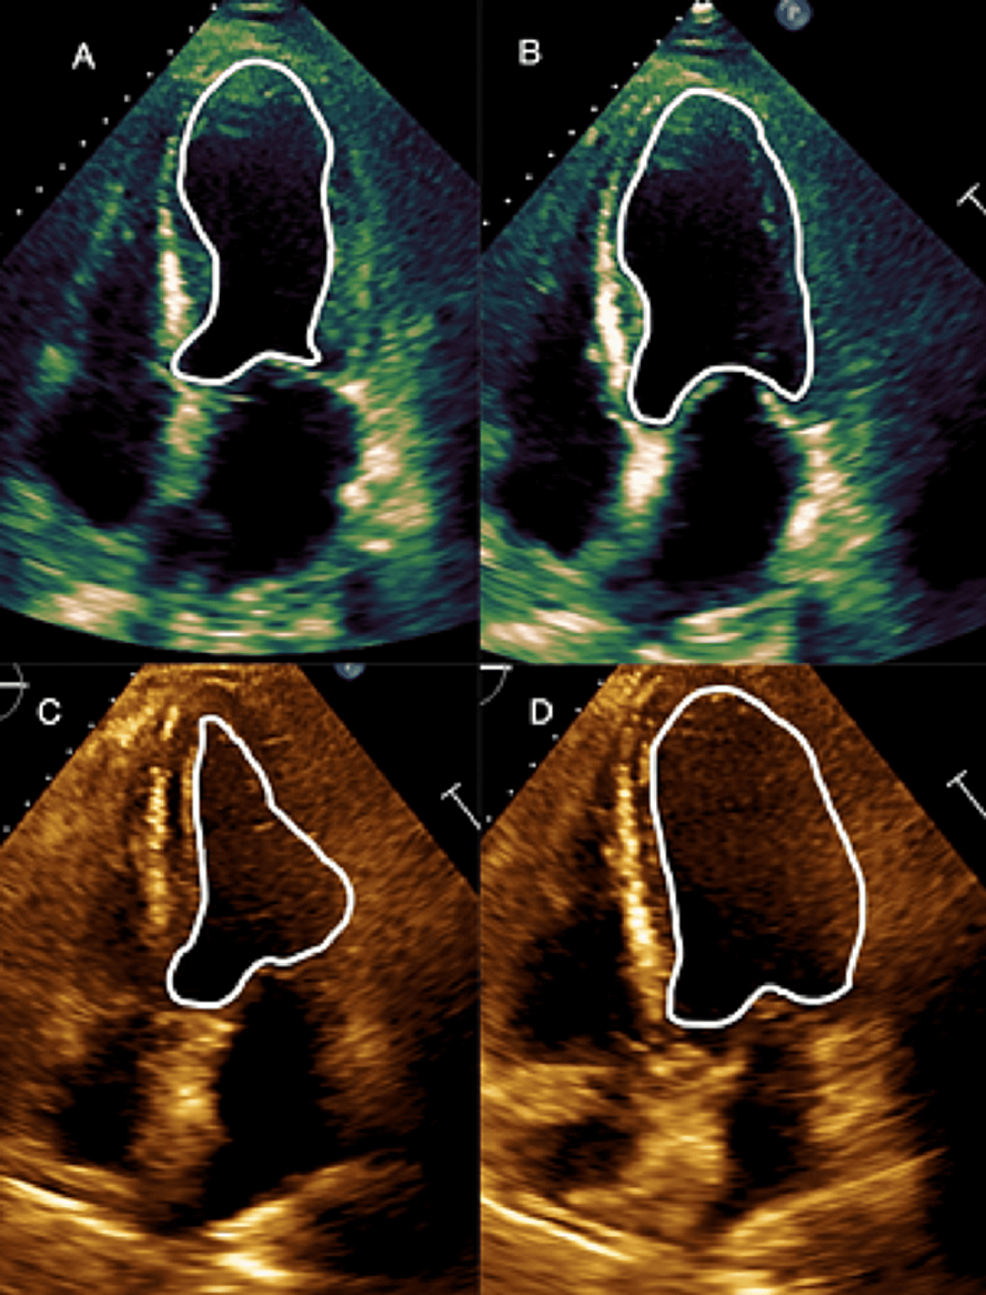

A Case Report and 31-Case Study: Does Takotsubo Cardiomyopathy in Myasthenia Gravis Patients Have a High Mortality Rate?

Myasthenia gravis is an autoimmune disorder in which antibodies are formed against post-synaptic nicotinic acetylcholine receptors that lead to impeded muscle contraction and commonly affects the oculomotor muscles. Takotsubo cardiomyopathy...

Relevance: We present a 66-year-old Caucasian male with a history of ocular myasthenia gravis who presented in a myasthenic crisis that was later diagnosed to have features suggestive of takotsubo cardiomyopathy.